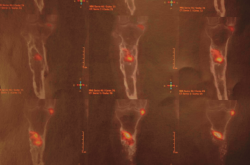

Figura 6. Estudio de SPECT-TAC-gammagrafía con leucocitos marcados. Se objetiva captación compatible con proceso séptico en el extremo proximal de la tibia.

Tras estudio de SPECT-TAC y gammagrafía con leucocitos marcados se objetiva foco séptico al nivel del extremo proximal de la tibia (Figura 6).